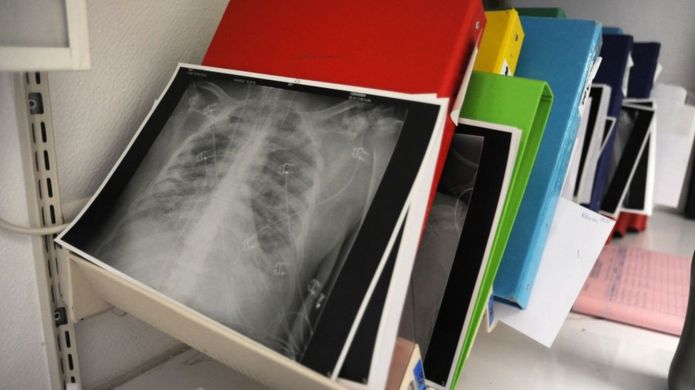

ދުނިޔޭގައި ފުރަތަމަ ފަހަރަށް ދިރިހުރި މީހެއްގެ ފަރާތުން، ކޮވިޑް ޖެހިފައިވާ މީހަކަށް ފުއްޕާމޭގެ ޓްރާންސްްޕްލާންޓެއް ހަދައިފިއެވެ.

ފުއްޕާމޭގެ ޓްރާންސްޕްލާންޓް ހެދީ ޖަޕާނުގެ އަންހެނަކު ކޮވިޑް ޖެހި، އޭނާގެ ފުއްޕާމޭ ބޭނުން ނުކުރެވޭވަރަށް ފެއިލްވުމުންނެވެ. މިގޮތަށް ގުނަވަން ފެއިލް ވުމުން މަރުވާ މީހެއްގެ ފަރާތުން ގުނަވަނެއް ހޯދުމަށް ވެއިޓް ލިސްޓު ކުރެވޭއިރު، ގުނަވަނެއް ލިބުމަށް އެތައް ދުވަހެއް ހޭދަވެއެވެ.

ނަމަވެސް، މަރުވާ މީހެއްގެ ފަރާތުން ގުނަވަނެއް ހޯދުމުގެ ބަދަލުގައި އޭނާއަށް ފުއްޕާމޭ ހަދިޔާ ކުރީ އޭނާގެ ފިރިހެން ދަރިފުޅާއި ފިރިމީހާއެވެ. 11 ގަޑިރުގެ އޮޕަރޭޝަނަކަށްފަހު، ފުއްޕާމޭގެ ބައެއް ހަދިޔާ ކުރި ފަރާތްތަކުންނާއި، ފުއްޕާމޭ ލިބުނު އަންހެންމީހާގެ ހާލު ރަނގަޅުކަމަަށް ޖަޕާނުގެ ކިޔޯޓޯ ޔުނިވަރސިޓީގެ ހޮސްޕިޓަލުން ބުނެފައިވެއެވެ.

މިއީ މިފަދައިން ދިރިހުރި މީހެއްގެ ފަރާތުން ގުނަވަނެއް ހަދިޔާކުރި ފުރަތަމަ ފަހަރު ކަމަށްވެއެވެ. ކޮވިޑާ ގުޅިގެން އާ ފުއްޕާމެއަކަށް ބޭނުންޖެހިފައިވާ އެތައް ބަޔަކު ދުނިޔޭގައި އެބަތިބިކަމަށްވެސް ވެެއެވެ.